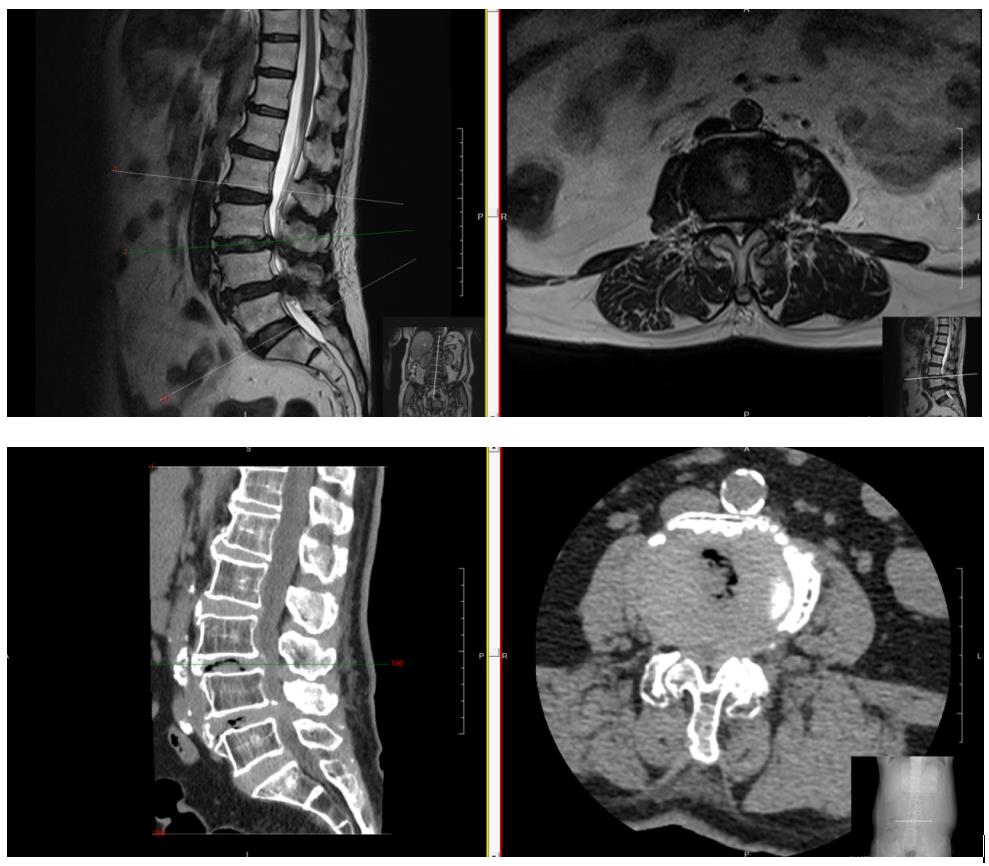

术中王义生主任通过内镜特有的放大效果,获得清晰的手术视野,即(在很小的切口内,通过内镜放大20倍以上视野,椎管外使用2至4mm直径器械,椎管内使用1至2mm直径器械进行操作。)在少出血、少剥离、高效率的条件下成功完成腰椎后路椎板减压椎间融合钉棒系统内固定术。手术历时2小时余,出血仅约100ml。手术效果显著,患者第二天就能戴支具下床活动,患者及家属对手术效果非常满意。

▲王义生主任在进行OSE脊柱内镜手术

▲术后第二天患者能戴支具下床活动